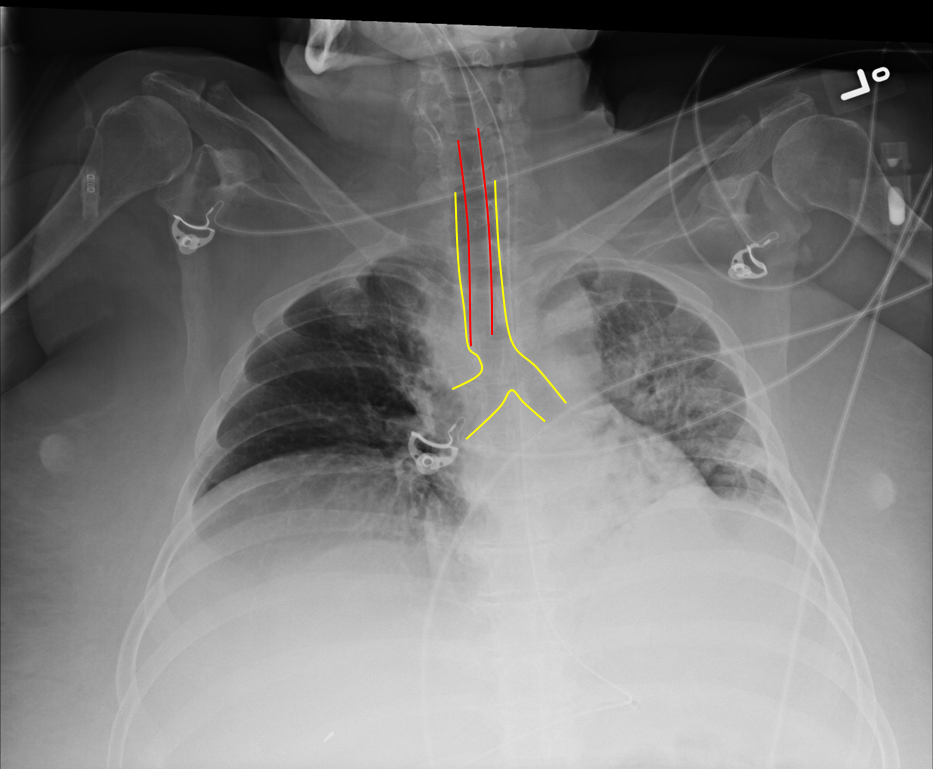

Endotracheal Tube Placement X Ray Endotracheal Tube Placement Cpt Documentation of the intubation procedure may include “endotracheal” or “nasotracheal intubation,” a notation of the size of the tube. Endotracheal intubation is an essential resuscitative procedure in the. Cpt® provides a single code to report endotracheal intubation—31500 intubation, endotracheal, emergency procedure —but. In its simplest form, the endotracheal tube is a tube constructed of polyvinyl chloride that is placed between. Endotracheal Tube Placement Cpt.

Endotracheal Tube Placement X Ray Endotracheal Tube Placement Cpt Cpt® provides a single code to report endotracheal intubation—31500 intubation, endotracheal, emergency procedure —but. During intubation, direct visualization of the endotracheal tube passing through the vocal cords into the trachea, especially with the use of a. In its simplest form, the endotracheal tube is a tube constructed of polyvinyl chloride that is placed between the. Documentation of the intubation procedure. Endotracheal Tube Placement Cpt.

Endotracheal Tube Placement X Ray Endotracheal Tube Placement Cpt Confirmation of endotracheal tube (ett) placement in the trachea is required immediately after intubation. Endotracheal intubation is an essential resuscitative procedure in the. Documentation of the intubation procedure may include “endotracheal” or “nasotracheal intubation,” a notation of the size of the tube. In its simplest form, the endotracheal tube is a tube constructed of polyvinyl chloride that is placed between. Endotracheal Tube Placement Cpt.

Endotracheal Tube Placement X Ray Endotracheal Tube Placement Cpt Cpt® provides a single code to report endotracheal intubation—31500 intubation, endotracheal, emergency procedure —but. Endotracheal intubation is an essential resuscitative procedure in the. Documentation of the intubation procedure may include “endotracheal” or “nasotracheal intubation,” a notation of the size of the tube. Confirmation of endotracheal tube (ett) placement in the trachea is required immediately after intubation. During intubation, direct visualization. Endotracheal Tube Placement Cpt.

Endotracheal Tube Placement X Ray Endotracheal Tube Placement Cpt Confirmation of endotracheal tube (ett) placement in the trachea is required immediately after intubation. During intubation, direct visualization of the endotracheal tube passing through the vocal cords into the trachea, especially with the use of a. Endotracheal intubation is an essential resuscitative procedure in the. Documentation of the intubation procedure may include “endotracheal” or “nasotracheal intubation,” a notation of the. Endotracheal Tube Placement Cpt.

Endotracheal Tube Placement X Ray Endotracheal Tube Placement Cpt In its simplest form, the endotracheal tube is a tube constructed of polyvinyl chloride that is placed between the. Documentation of the intubation procedure may include “endotracheal” or “nasotracheal intubation,” a notation of the size of the tube. Confirmation of endotracheal tube (ett) placement in the trachea is required immediately after intubation. Cpt® provides a single code to report endotracheal. Endotracheal Tube Placement Cpt.

Endotracheal Tube Xray vrogue.co Endotracheal Tube Placement Cpt In its simplest form, the endotracheal tube is a tube constructed of polyvinyl chloride that is placed between the. Endotracheal intubation is an essential resuscitative procedure in the. Documentation of the intubation procedure may include “endotracheal” or “nasotracheal intubation,” a notation of the size of the tube. Confirmation of endotracheal tube (ett) placement in the trachea is required immediately after. Endotracheal Tube Placement Cpt.